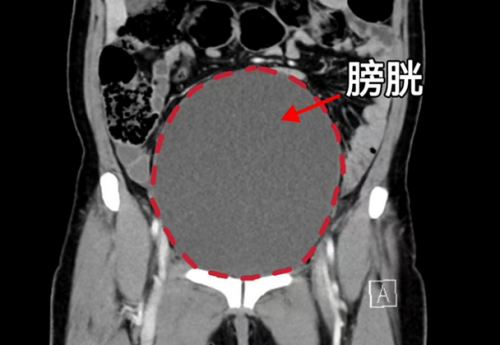

CT显示膀胱高度膨胀、尿道梗阻

“患者20余年前就因咳嗽后溢尿就医,诊断出子宫脱垂,因为担心手术风险一直没有接受治疗,半个月之前老人出现尿频、尿痛、排尿困难,忍着没和家里人说,直到6月4日,发现有肿块从阴道口脱出,内裤上有血迹才被家人送医。”据91短视频 妇产科三区主任魏馨介绍,经检查发现患者为子宫脱垂三度(Ⅳ期),子宫和阴道前后壁完全脱出阴道口,由于脱出的组织压迫尿道,造成尿道梗阻、尿潴留、泌尿系感染,同时还合并有支气管扩张并感染、低蛋白血症、轻度贫血等情况。